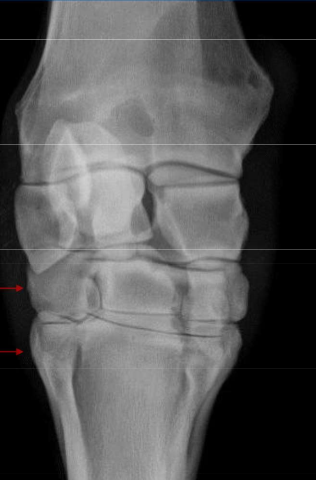

What is this lesion

OCD of the distal intermediate ridge of the tibia in the hock